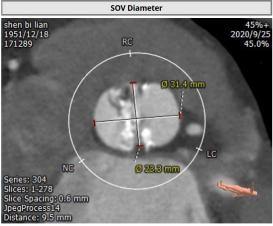

CT:

主动脉瓣Type 0型二叶瓣,瓣叶瓣缘结节样增厚伴中度钙化,开放受限。冠脉高度可。法式窦结构可,心脏角度约52°,左室较小,升主动脉未见明显扩张,右股动脉直径大于5.5mm,可作为主入路。患者为中度钙化的,重度主动脉瓣狭窄,呈鱼嘴型,结合主动脉根部结构,考虑植入Sapien 3瓣膜。

法式窦

窦管结合部